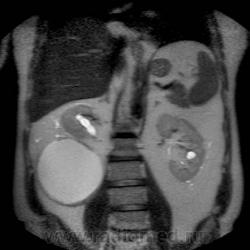

Кистозно-солидное образование н/3 правой почки, солидный компонент хоть и минимальный, но он есть, следует с ним внимательнее разобраться, я бы отнес данное кистозное образование к IV категории по Босняку.

А. эта опухоль больше похожа на "добро" или "зло"?

Добрый вечер. Босняк 4 означает что образование надо рассматривать как злокачественное, пока не будет доказано обратное или подтверждена злокачественная природа.

Сто процентный рак. Без всяких босняков.

Я бы в диф ряде рассмотрел бы эхинококкоз - в нижнем полюсе образования есть перегородка.

А вот метастазов рака почки, по видимому, не видит никто) а они есть)

Пока нет данных морфологии по этой кисте - не отказываюсь от своего мнения об эхинококке. Статьи по изолированому эхинококку почек(всего 3 процента по статистике) и других редких локализаций можно посмотреть здесь http://ifolder.ru/21262829, если кому-то еще интересна дискуссия